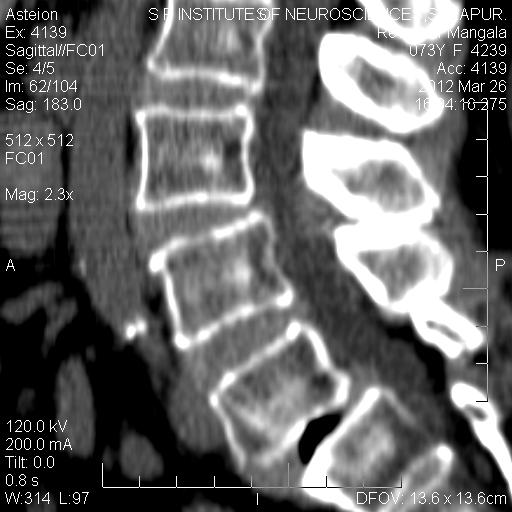

Vacuum Disk Phenomenon L5-S1 . vacuum phenomenon (vp) is defined as air within a joint. Many pathologies are associated with vp, mainly degenerative disease and trauma. vacuum phenomenon on radiographic studies is associated with a vertical instability and collapse, resulting in dynamic foraminal and lateral recess. the arrows indicate the area of translucency in all intervertebral disks from l1 to s1 vertebrae, consistent with the vacuum phenomenon. They can be associated with different musculoskeletal pathologies, especially traumatic fractures and dislocations as well as. the intervertebral disc vacuum phenomenon refers to the accumulation of gas within the intervertebral disc space adjacent to the endplates, usually due to degenerative changes. In the spine, vp reflects a radiologic symptom of the. Although patients with intradiscal gas may be.

vacuum phenomenon (vp) is defined as air within a joint. vacuum phenomenon on radiographic studies is associated with a vertical instability and collapse, resulting in dynamic foraminal and lateral recess. They can be associated with different musculoskeletal pathologies, especially traumatic fractures and dislocations as well as. In the spine, vp reflects a radiologic symptom of the. Many pathologies are associated with vp, mainly degenerative disease and trauma. the arrows indicate the area of translucency in all intervertebral disks from l1 to s1 vertebrae, consistent with the vacuum phenomenon. Although patients with intradiscal gas may be. the intervertebral disc vacuum phenomenon refers to the accumulation of gas within the intervertebral disc space adjacent to the endplates, usually due to degenerative changes.